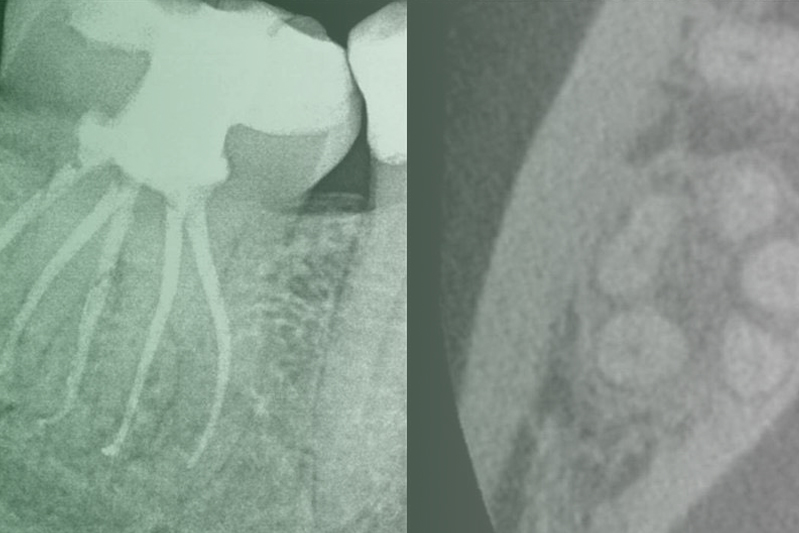

Клинический случай. Эндодонтия

01 апреля 2020